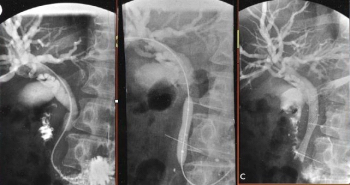

| תצלום 16.8: ניקוז דרכי המרה. תמונה ימנית בעזרת צנתר תמונה שמאלית הכנסת תותב (סטנט) לדרכי המרה | |

- בשיטה זו מחדירים אנדוסקופ דרך הפה לתריסריון, מזהים את הפפילה על-שם ואסר, ולתוכה מחדירים צנתר שדרכו מזריקים חומר ניגוד לדרכי המרה וללבלב. ההדגמה היא רנטגנית (תצלום 12.8- 11.8) וניתן לראות בה הרחבה של דרכי המרה, או אבנים (תצלום 13.8) או שאתות בדרכי המרה, או חסימות של דרכי המרה (תצלום 14.8). אפשר להדגים את כיס המרה והפתולוגיות שבתוכו.

- אם מודגמת אבן בדרכי המרה, אפשר לבצע בזמן הבדיקה:

- פפילוטומיה אנדוסקופית (Endoscopic papillotomy) - חיתוך של הפפילה לאורכה והרחבתה. הרחבה זו מאפשרת ניקוז טוב יותר של דרכי המרה, וכן היא מאפשרת לאבן שנתקעה במעבר הצר של הפפילה לעבור לתריסריון.

- שליפה של אבנים בעזרת מכשירים כגון Basket או ריסוק הגדולות שבהן ולאחר מכן שליפת הפירורים (תצלום 15.8).

- כשאין אפשרות לחדור לפפילה עקב סתימה שלה, אפשר בזמן ה- ERCP לבצע חתך מעל הפפילה לכולדוכוס (Precut), להחדיר את הצנתר דרכו וכך להדגים את דרכי המרה. אם יש חשד לשאת בדרכי המרה או בלבלב, אפשר בזמן ה- ERCP לגרד מהנגע במברשת מיוחדת חומר מהשאת ולשלוח אותו לאבחון ציטולוגי (Brush cytology).

- הכנסת נקז לדרכי המרה בחולים עם חסימה על מנת לנקז את דרכי המרה באופן זמני או קבוע (תצלום 16.8)

| תצלום 18.8: MRCP מדגים את העץ ביליארי והאנטומיה שלו. תצלום שמאלי מראה את האנטומיה של דרכי המרה והלבלב. תצלום ימני חץ מראה חסר בצינור המרה המשותף D - תריסריון G - כיס מרה. | |